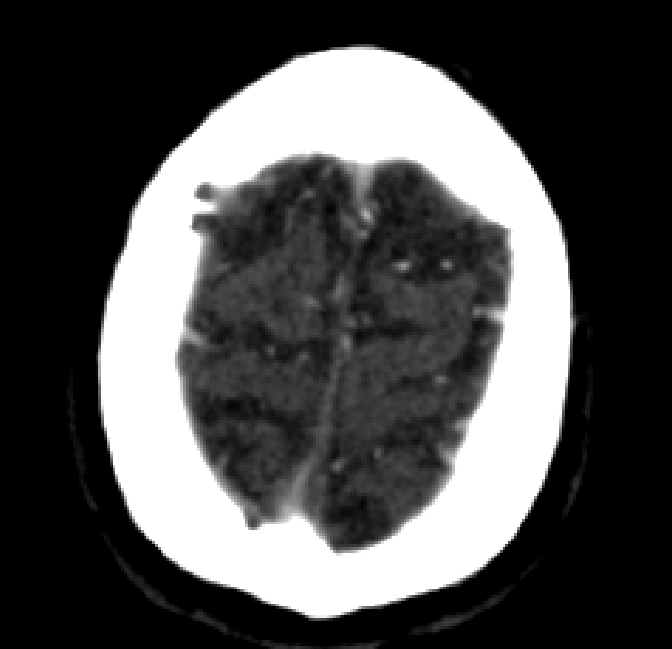

After fine-tuning, the two pre-train conditions appear to have little or no difference in terms of qualitative performance at the vessel segmentation task. However, when compared to the models trained only on real data, there are noticeable differences. Throughout Figures 4.3-4.9, the model pre-trained on scans with original CT noise is to be taken as representative of segmentation performed by the Perlin noise pre-training condition. Images showing the hand-labeled ground truth, as well as the unlabeled slice, are presented for comparison.

Figure 4.7: Segmentations on regions near the top of the skull. Unaltered image (left). No pretrain model (mid-left). Fine-tuned model (mid-right). Hand-labeled ground truth (right).

The models appear to have a hard time segmenting vessels close to the skull surface. The model trained exclusively on patient data appears to struggle far more for these types on conditions than the fine-tuned models. Figure 4.8 shows an example of the fine-tuneds model having close to no trouble segmenting vessels near the left side of the skull, while the baseline model suffers heavily from false negatives. To lesser degree, this effect can also be observed in the frontal lobe of Figure 4.9 In the other hand, Figure 4.7 presents an example of both models failing to segment vessels near the top of the skull.